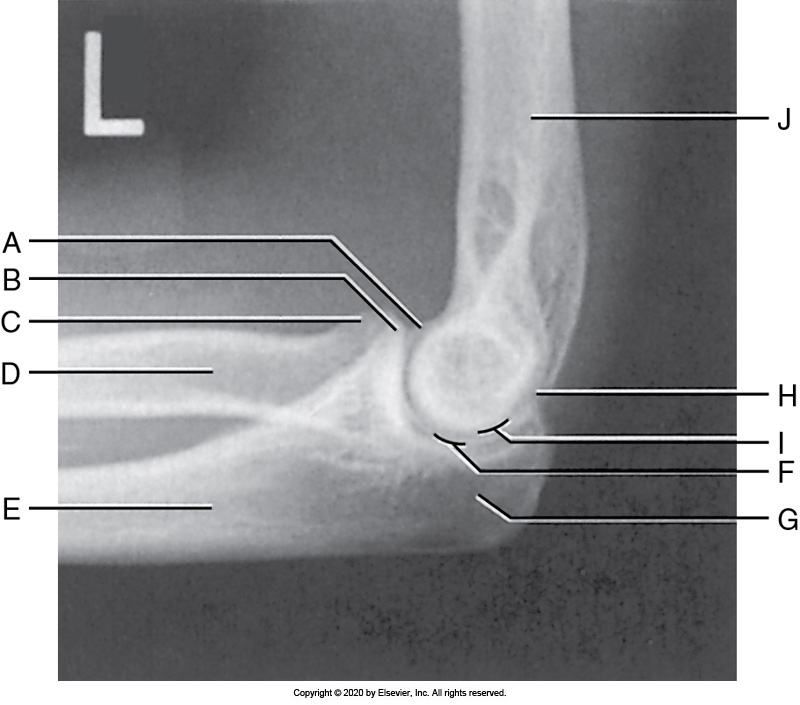

Identify the labeled "H" anatomy inn the image below:

Capitulum

Identify the labeled "D" anatomy in the image below:

Medial epicondyle